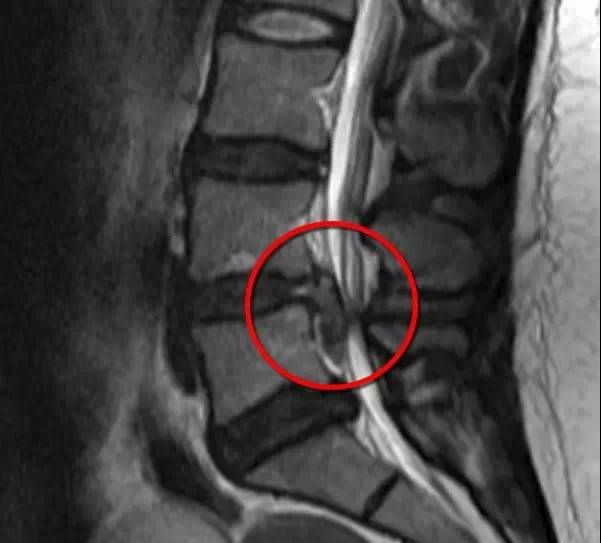

腰椎间盘突出症是常见的疾患,主要是因为腰椎间盘各部分老化退变后,在外力因素的作用下,椎间盘的纤维环破裂,髓核组织从破裂之处突出于后方或椎管内,导致相邻脊神经根受刺激或压迫,从而产生腰部疼痛,一侧下肢或双下肢麻木、疼痛等一系列临床症状,MRI上可以清楚的看见突出的椎间盘。

腰椎间盘突出MRI